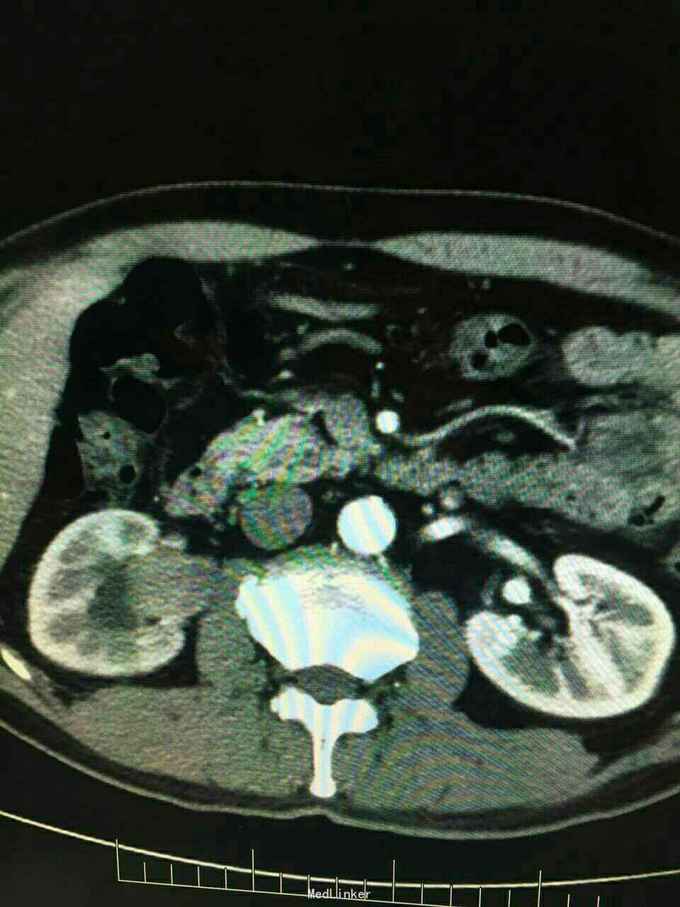

超声示:右肾积水,右肾盂内可见异常回声,不除外新生物,前列腺增生。CT示:右肾门占位,累及邻近肾实质并右肾积水,右肾排泄功能受损,考虑右肾肾盂肿瘤性病变。初步诊断为:1.右肾盂肿瘤(TI1N0M0)2.右肾积水 3.前列腺增生。